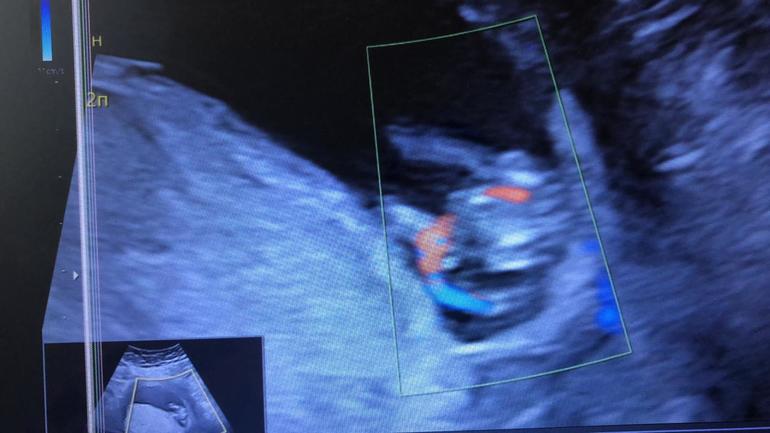

Это Фото с узи и ниже скрин.

Снимали попу долго😅ножки влево идут.

Как думаете, кто там?)

Мне кажется я вижу пирожок😅